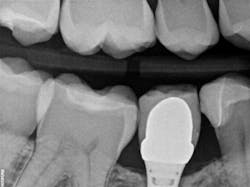

When decay arises on adjacent teeth, dentists must evaluate their treatment options. I have found there is a high degree of difficulty restoring large Class II or interproximal lesions with direct composites, especially when the decay is on premolars. It is much more predictable to restore Class IIs on molars with tight contacts, but it can still be difficult. I have tried full matrix bands and multiple sectional matrix bands, but I can’t create a nice contour with a tight contact. I have even tried traditional composites and bulk fill without great success. See Figures 1 and 2 showing my open contacts with direct composite.

present at DL line angle not seen on radiograph.

food debris in the contact area.